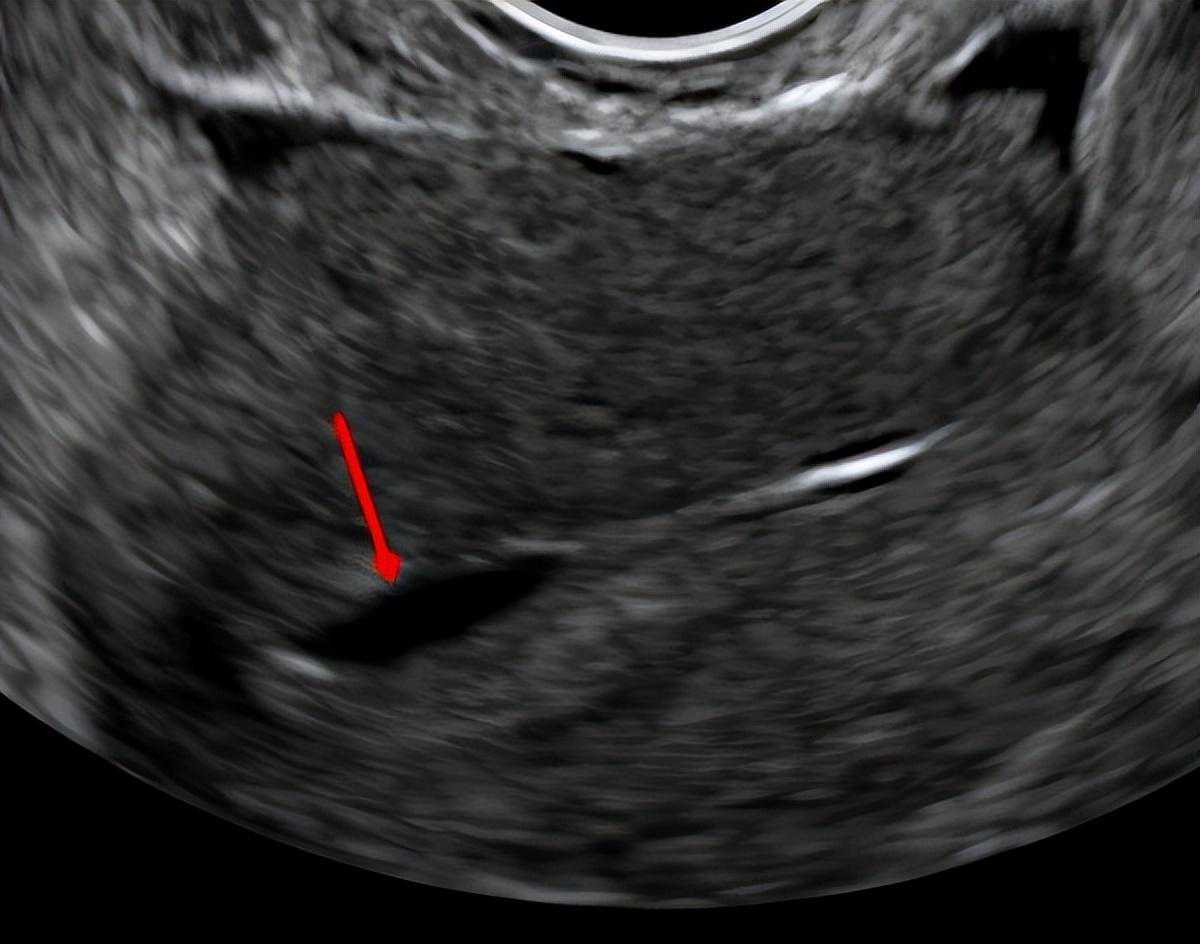

4、子宫腔内的积液干扰

子宫内膜的细胞会不断地产生液体,其中一些液体被子宫内膜中的细胞重新吸收,一些液体通过子宫颈从子宫渗漏到阴道,一些液体通过输卵管渗漏到腹部。然而,在某些情况下,额外的液体可能会积聚在腔内。如果子宫腔中充满这些液体,这会减少胚胎着床的机会。

子宫腔内的液体

在一些女性中,子宫腔内积液可能是由于输卵管末端堵塞导致的,这被称为输卵管积水。输卵管积水有毒性作用,会降低胚胎着床率,因此,在移植前需要处理输卵管积水。解决方法一般是进行手术切除输卵管,这是一种经过充分研究的治疗方法,可以使怀孕的机会增加一倍。

在没有输卵管积水的情况下,清除子宫腔内的积液更具挑战性。如果在服用雌激素期间存在液体,那么开始使用黄体酮通常会导致多余的液体被重新吸收,胚胎移植可以正常进行。

如果这些积液继续存在,取消这个周期、待下一个周期再移植可能是谨慎的做法。